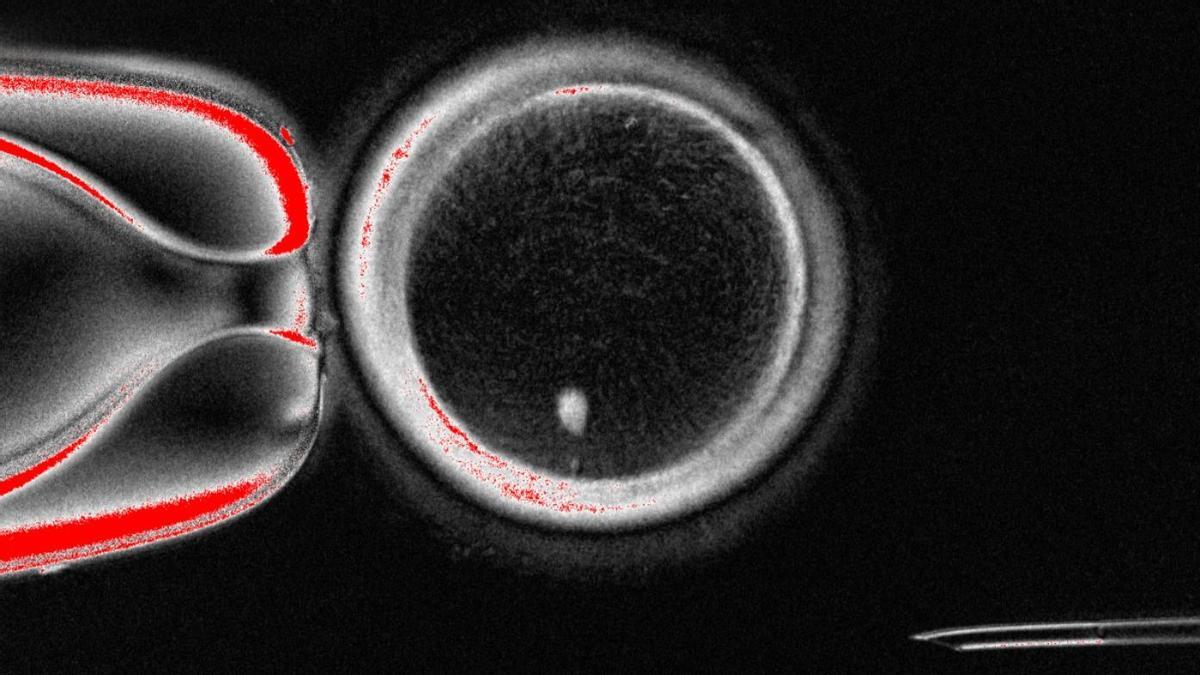

Ovocito humano generado a partir de células de la piel. / Laboratorio Mitalipov / Nature

El procedimiento, ideado por el equipo del investigador Shoukhrat Mitalipov, de la Universidad de Salud y Ciencias de Oregón, consiste en extraer células de la piel de un paciente y reprogramarlas para convertirlas en óvulos funcionales. Según explican los creadores de esta herramienta, el proceso empieza extrayendo el núcleo de una célula cutánea, donde se guarda el ADN del paciente, y colocándolo dentro de un óvulo donado al que previamente se le ha quitado su propio núcleo. Entonces, para era evitar que la nueva célula tenga el doble de cromosomas de lo normal, los científicos han desarrollado un procedimiento experimental llamado 'mitomeiosis' que reproduce los pasos de la división celular natural y elimina el exceso de cromosomas, dejando así un óvulo con la carga genética correcta.

En total, a partir de esta técnica, los científicos reportan la creación de hasta 82 ovocitos funcionales a partir de células somáticas. En el marco de este experimento, los científicos fecundaron estos óvulos con espermatozoides en condiciones de laboratorio. Solo una pequeña proporción, que según se describe en el artículo ronda el 9%, logró desarrollarse hasta el estadio de blastocisto, el equivalente al sexto día tras la fecundación y al estadio a partir del cual, hasta ahora, una fecundación in vitro tradicional se procedería a transferir al útero. Los científicos explican que los embriones no se cultivaron más allá de este punto, en cumplimiento con la normativa vigente, pero que todo apunta a que serían viables a largo plazo y que, en definitiva, podrían dar lugar a un nacimiento como el de cualquier otra técnica 'in vitro'.